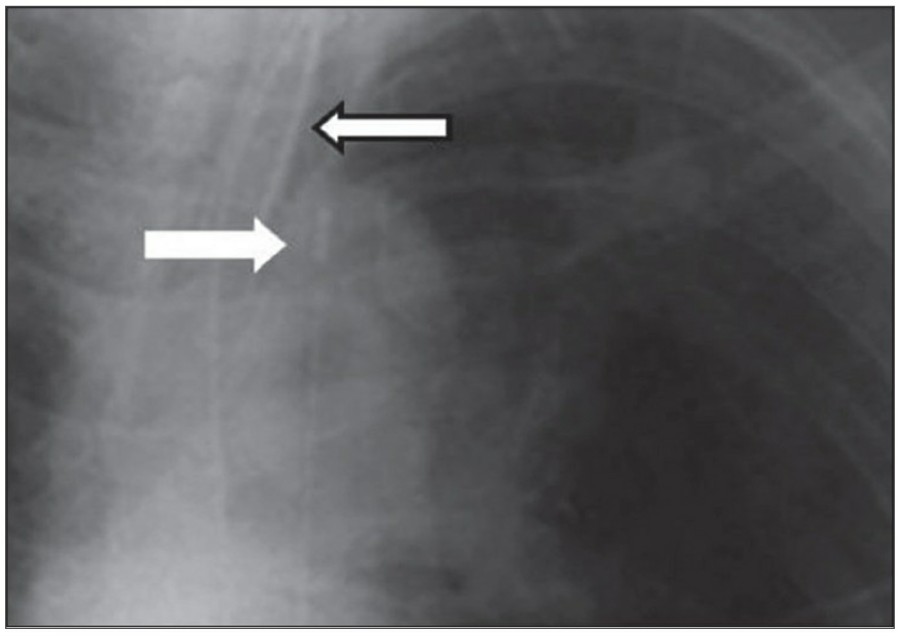

중환자에서 pneumothorax의 진단은 종종 supine radiograph에서 내릴 수 있다. Supine position에서 공기는 anteromedial 방향으로 모이게 되는데, apical air collection이 있을 경우 large pneumothorax가 있음을 시사한다. 공기는 lung과 diaphragm 사이의 subpulmonic location에 trap 되어 있을 수도 있다. 공기가 costophrenic sulcus로 anterolateral extension 될 경우, 이 costophrenic sulcus의 radiolucency를 증가시키는데, 이를 deep sulcus sign이라고 한다. Subpulmonic pneumothorax의 다른 특징으로 diaphragm의 superior surface와 IVC 윗부분이 뚜렷하게 보일 수 있다.